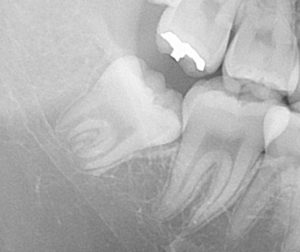

右下の親知らずです。

斜めに生えてきています。

まだ年齢が若いために、歯の根っこが未形成(作っている途中)です。

赤丸の位置に親知らずが潜っています。

親知らずに押されて、手前の歯が矢印方向に動いてズレてきています。

早めの抜歯が推奨されます。